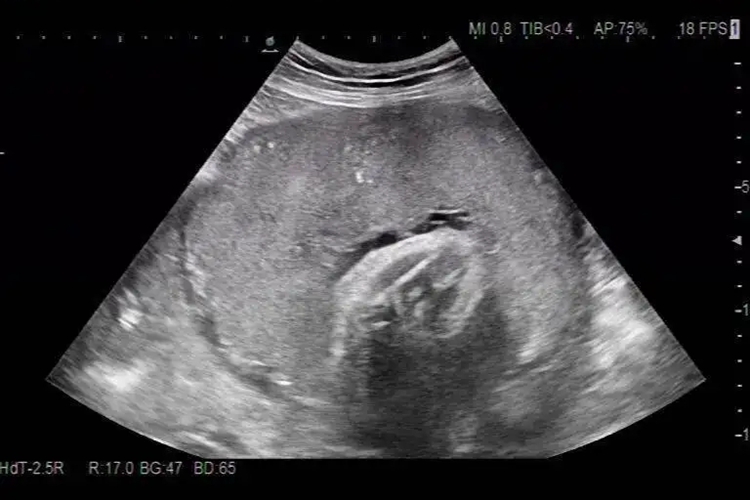

轮状胎盘是胎盘异常发育的一种现象,超声显示胎盘的特征性声像改变,胎儿面中心内凹,周围环绕灰白色环。

轮状胎盘是指胎儿面中心内凹,周围环绕增厚的灰白色环状胎盘。超声检查显示轮状胎盘的特征性声像改变,胎盘边缘呈环状或片状,突向羊膜腔,内部回声与胎盘实质回声相似,有出血或梗死者,内部可显示出无回声或低回声区。